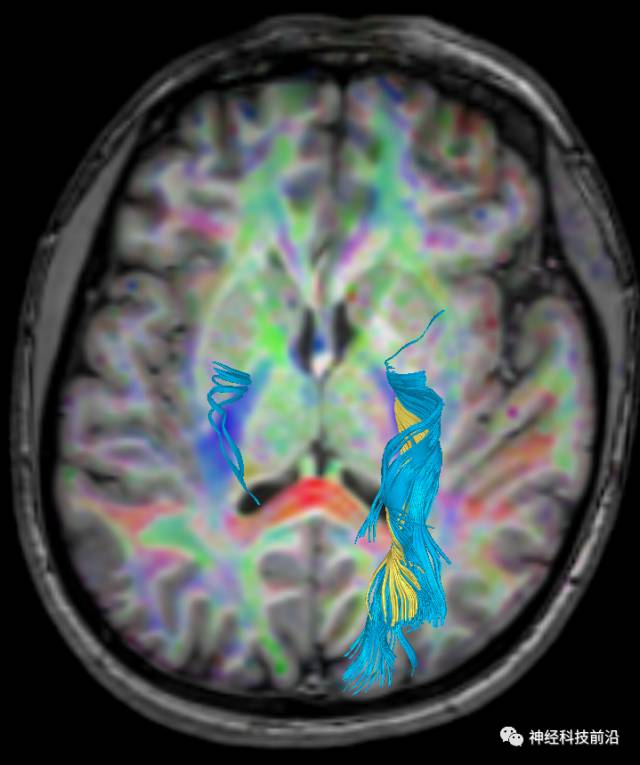

皮质脊髓束与皮质脑桥束的关系毗邻

终上所述:脑干高信号为一近环形纤维束,内囊后肢高信号为皮质脑桥束,皮质脊髓束在中脑位置略靠后。高信号位于中脑前缘,是皮质脑桥束的位置所在,另外有部分桥连纤维。